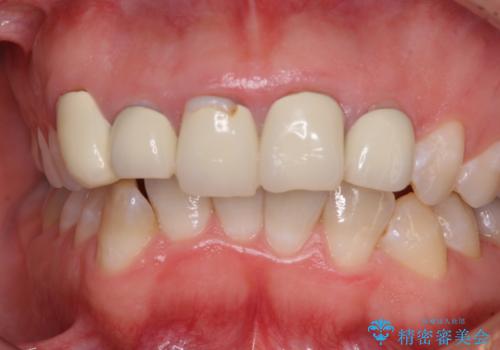

- 歯列不正を改善する目的で装着した前歯のセラミックが気になるとのことで来院された患者様です。

金属の裏打ちを用いたセラミッククラウンであったため歯肉縁に黒ずみが見えてくることは良くありますが、全体的に歯列が不揃いであることが気になったので、それらをオールセラミッククラウンにて改善することとしました。

セラミッククラウンが外れてしまうことを心配して、歯ブラシをあまり当てられなかったとのことで、歯肉に軽度の炎症が認められました。